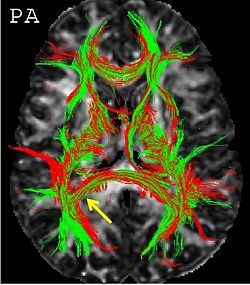

Non-linear registration of dMR